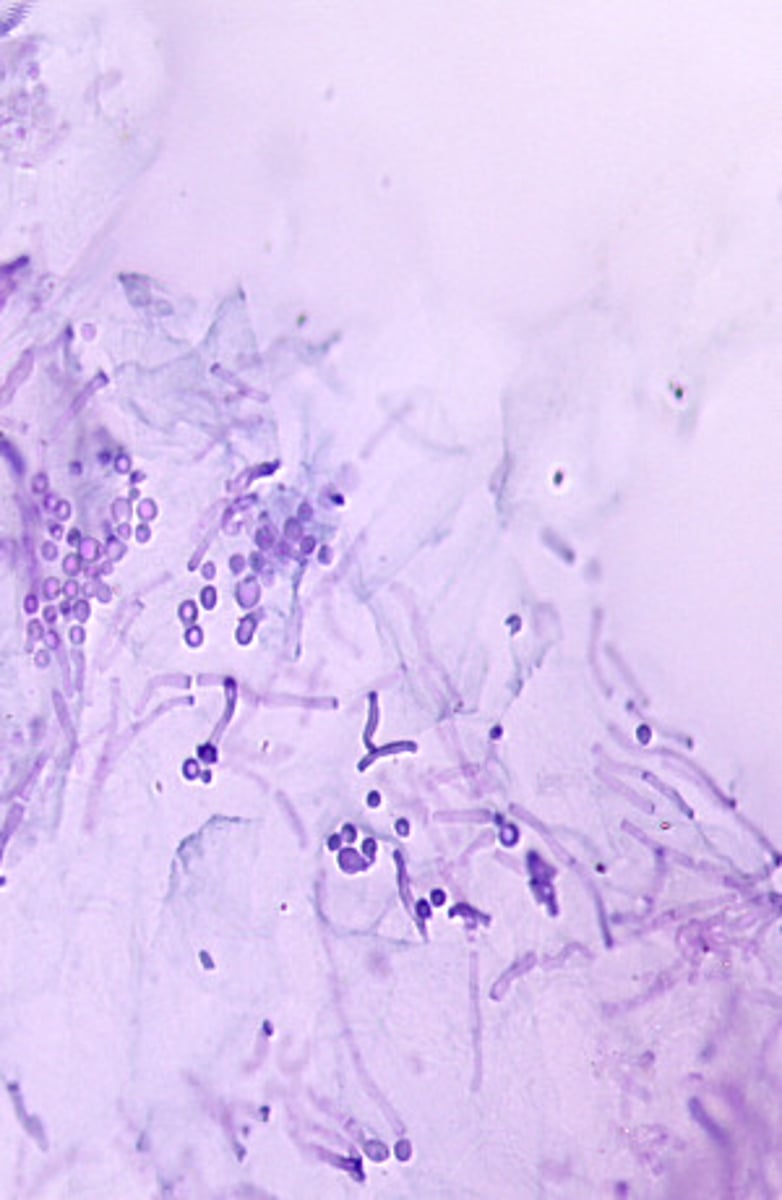

This microscopic image suggests which of the following?

Epidermophyton floccosum produces clusters of smooth, club-shaped macroconidia. The cell walls of Epidermophyton are thicker than those of the genus Trichophyton.